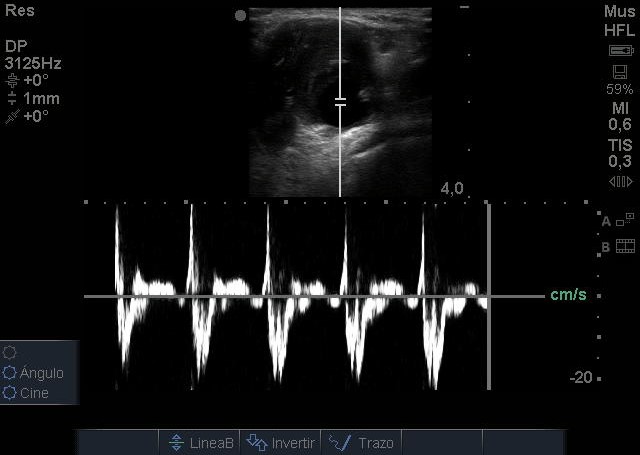

Se visualiza aneurisma de 2 centímetros con imagen compatible con trombo intramural. En modo Doppler flujo turbulento. Realizamos ecografía de rodilla contralateral y aórtica sin hallazgos reseñables.

Juicio Clínico: Aneurisma poplíteo con trombo intramural.